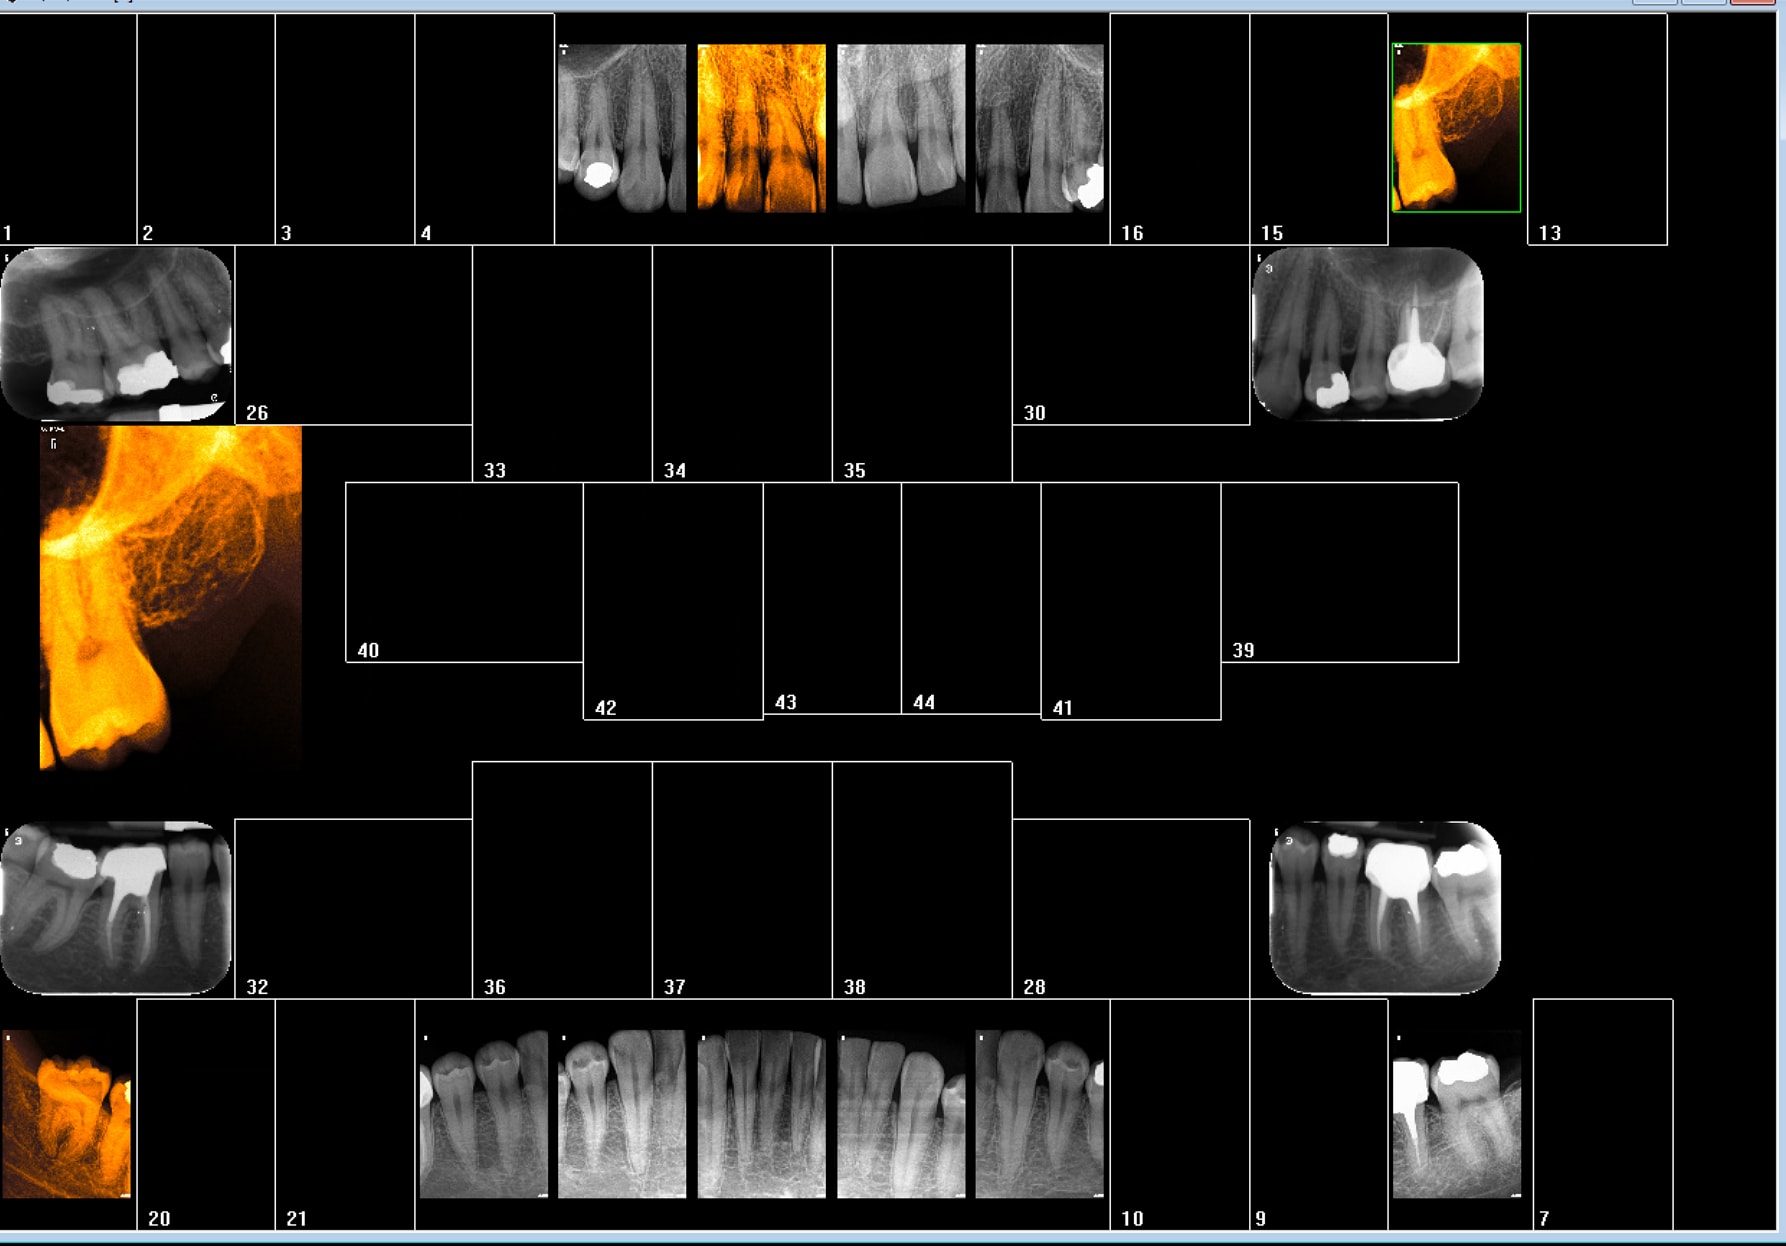

Ici quel examen radiologique est justifié ? pano ou status complet ? ou rétro coronaires + rétro alvéolaires ciblées ? Hein ?

>Ici quel examen radiologique est justifié ? pano ou status complet ? ou rétro coronaires + rétro alvéolaires ciblées ? Hein ?<

Not'chicot qui continue sa croisade contre la pano!!!

La carie distale passe avant l'ameloblastome, les dents ectopiques, la présence ou non de certains germes, la motivation, c'est sur!!!!